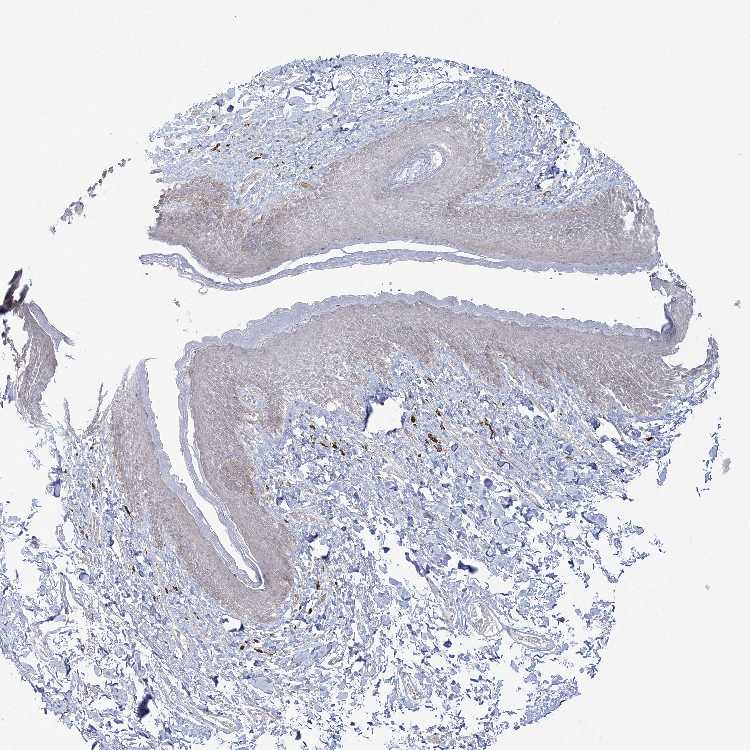

SKIN 1 - Antibody stainingi

Antibody staining in the annotated cell types in the current human tissue is reported as not detected, low, medium, or high, based on conventional immunohistochemistry profiling in selected tissues. This score is based on the combination of the staining intensity and fraction of stained cells.

Each image is clickable and will lead to virtual microscopy that enables deeper exploration of all samples and also displays staining intensity scores, fraction scores and subcellular localization as well as patient and tissue information for each sample.

Antibody HPA036677Antibody HPA036678Antibody HPA061398

Langerhans Not detectedNot detectedNot detected

Fibroblasts Not detectedNot detectedNot detected

Keratinocytes Not detectedNot detectedLow

Melanocytes Not detectedNot detectedLow

SKIN 2 - Antibody stainingi

Epidermal cells Not detectedNot detectedLow